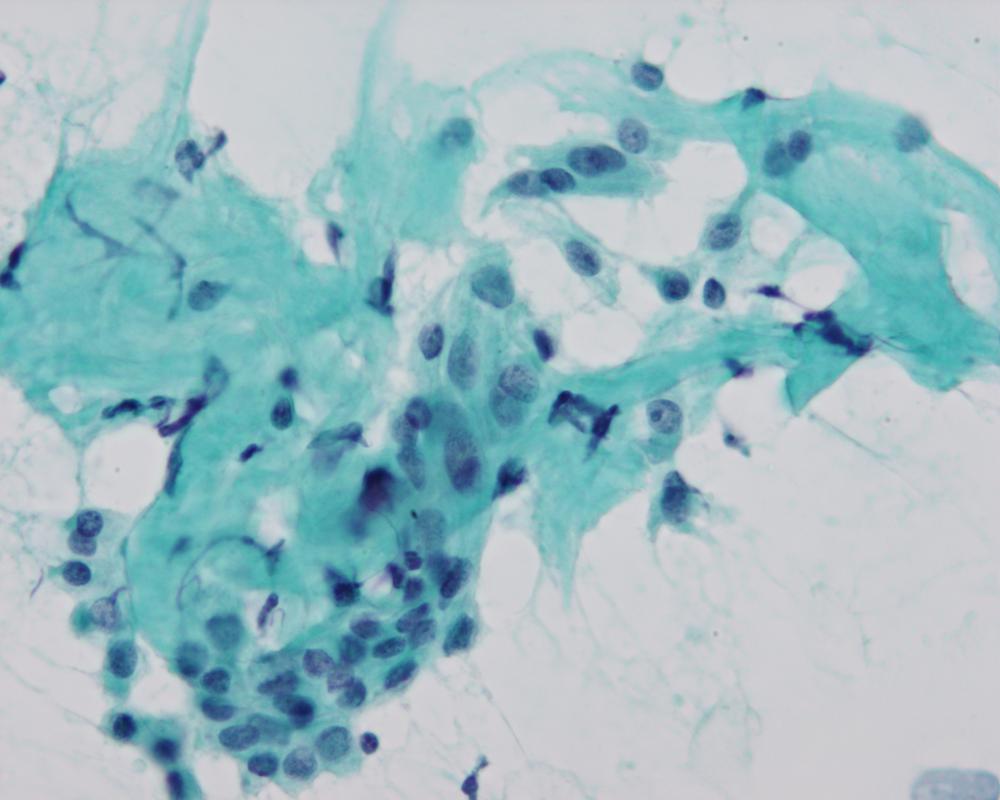

種別:甲状腺

出題:○黒濱 大和 長崎大学病院病理診断科・病理部

| 年齢 | 70代 | 性別 | 女性 |

| 採取部位 | 甲状腺 | 採取方法 | 穿刺吸引 |

| 検体処理法 | 従来法 |

既往歴:甲状腺左葉良性腫瘍切除(詳細不明,35歳時)

現病歴:1週間前より頸部腫脹を自覚。頸部に軽度圧痛のある弾性硬,可動性不良の8.5x5.0cmの腫瘤を認め,画像上甲状腺右葉に石灰化を伴う腫瘍を認めた。同部より細胞診が施行された。

| 正解 | 2.乳頭癌+未分化癌 |

| 1.乳頭癌 | 21件 | (26.2%) | |

| 2.乳頭癌+未分化癌 | 8件 | (10.0%) | |

| 3.低分化癌 | 9件 | (11.2%) | |

| 4.円柱細胞癌 | 35件 | (43.8%) | |

| 5.卵巣癌転移 | 7件 | (8.8%) | |

| 投票総数 | 80件 | (100%) |